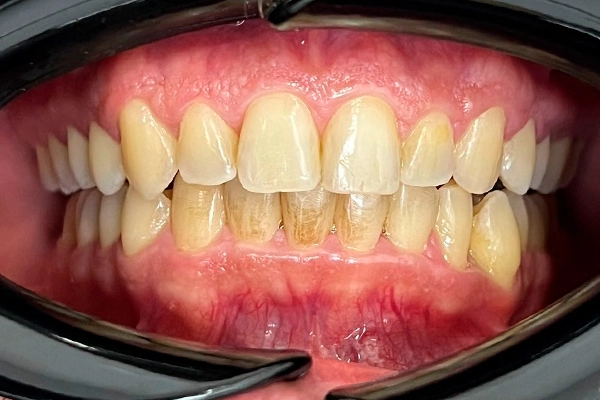

Conoce el antes y después de nuestros tratamientos